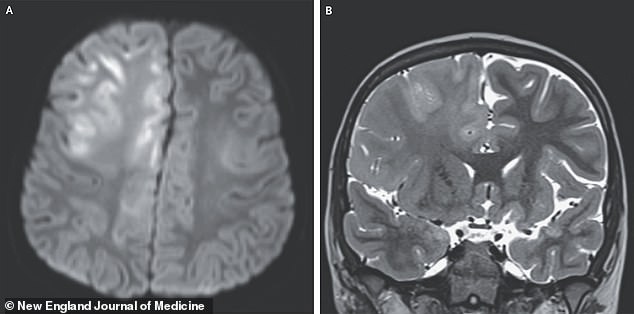

A case study from Children's Hospital of Orange County reveals the grim reality. A seven-year-old boy, infected with measles at seven months old in Afghanistan, later developed SSPE. His symptoms—seizures, cognitive decline, and spasming reflexes—were unrelenting. An MRI showed severe brain damage in the frontal lobe and corpus callosum. SSPE progresses slowly, with most patients surviving only four years after symptoms begin. What warnings did experts issue about this silent killer, and why were they ignored?